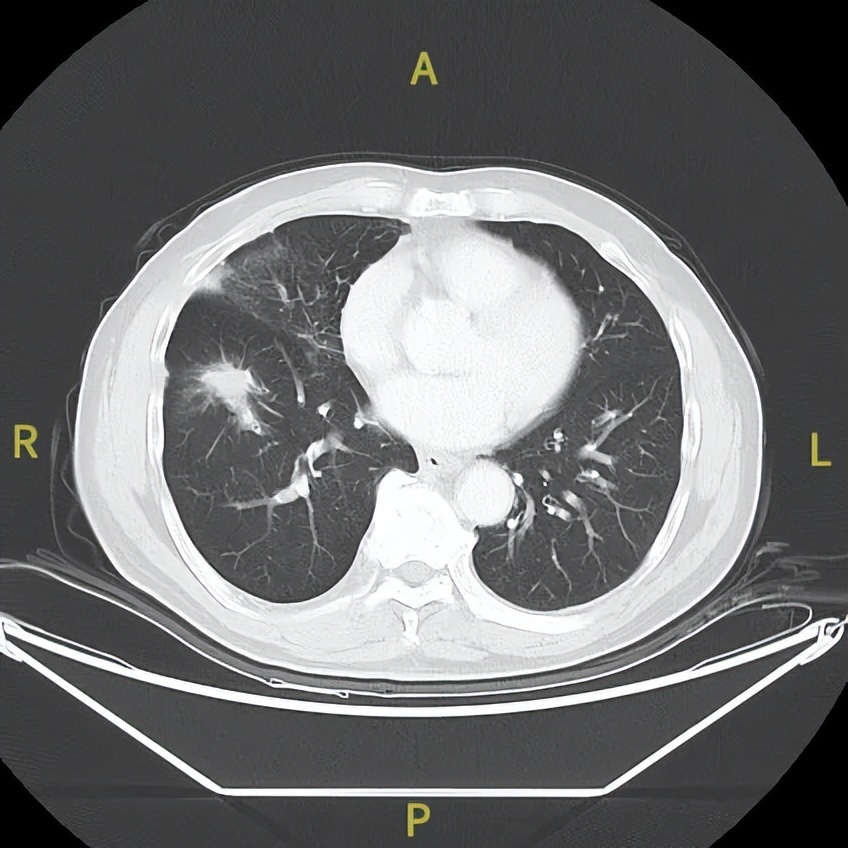

2023年1月31日

△治疗后不同随访时间的胸部及髋关节CT病灶变化